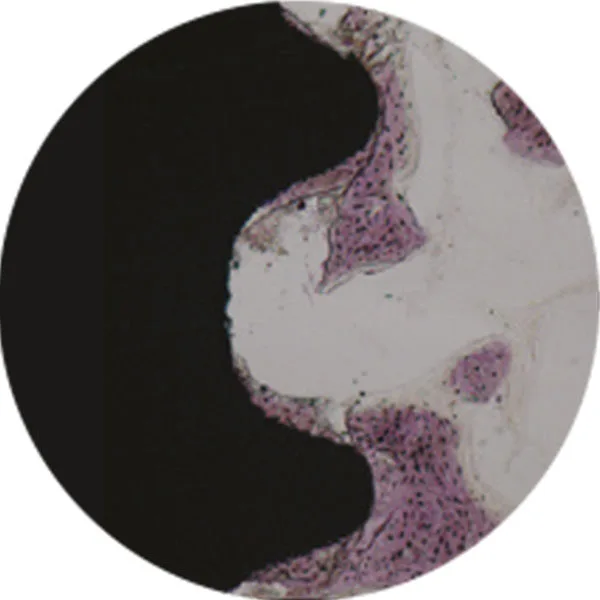

SA Surface

NH Surface

Significant Improvements to BIC

The super hydrophlic bioresorbable apatite increases Bone to Implant Contact (BIC) by 39% compared to SA.

Hydrophobic (1 minute after blood immersion)

Super Hydrophilic (1 minute after blood immersion)

After 2 weeks (Coating layer is present)

After 6 weeks (Coating layer is absorbed)

Bioresorbable apatite

Bone forms directly to the SA surface as the apatite layer is resorbed during osseointegration.